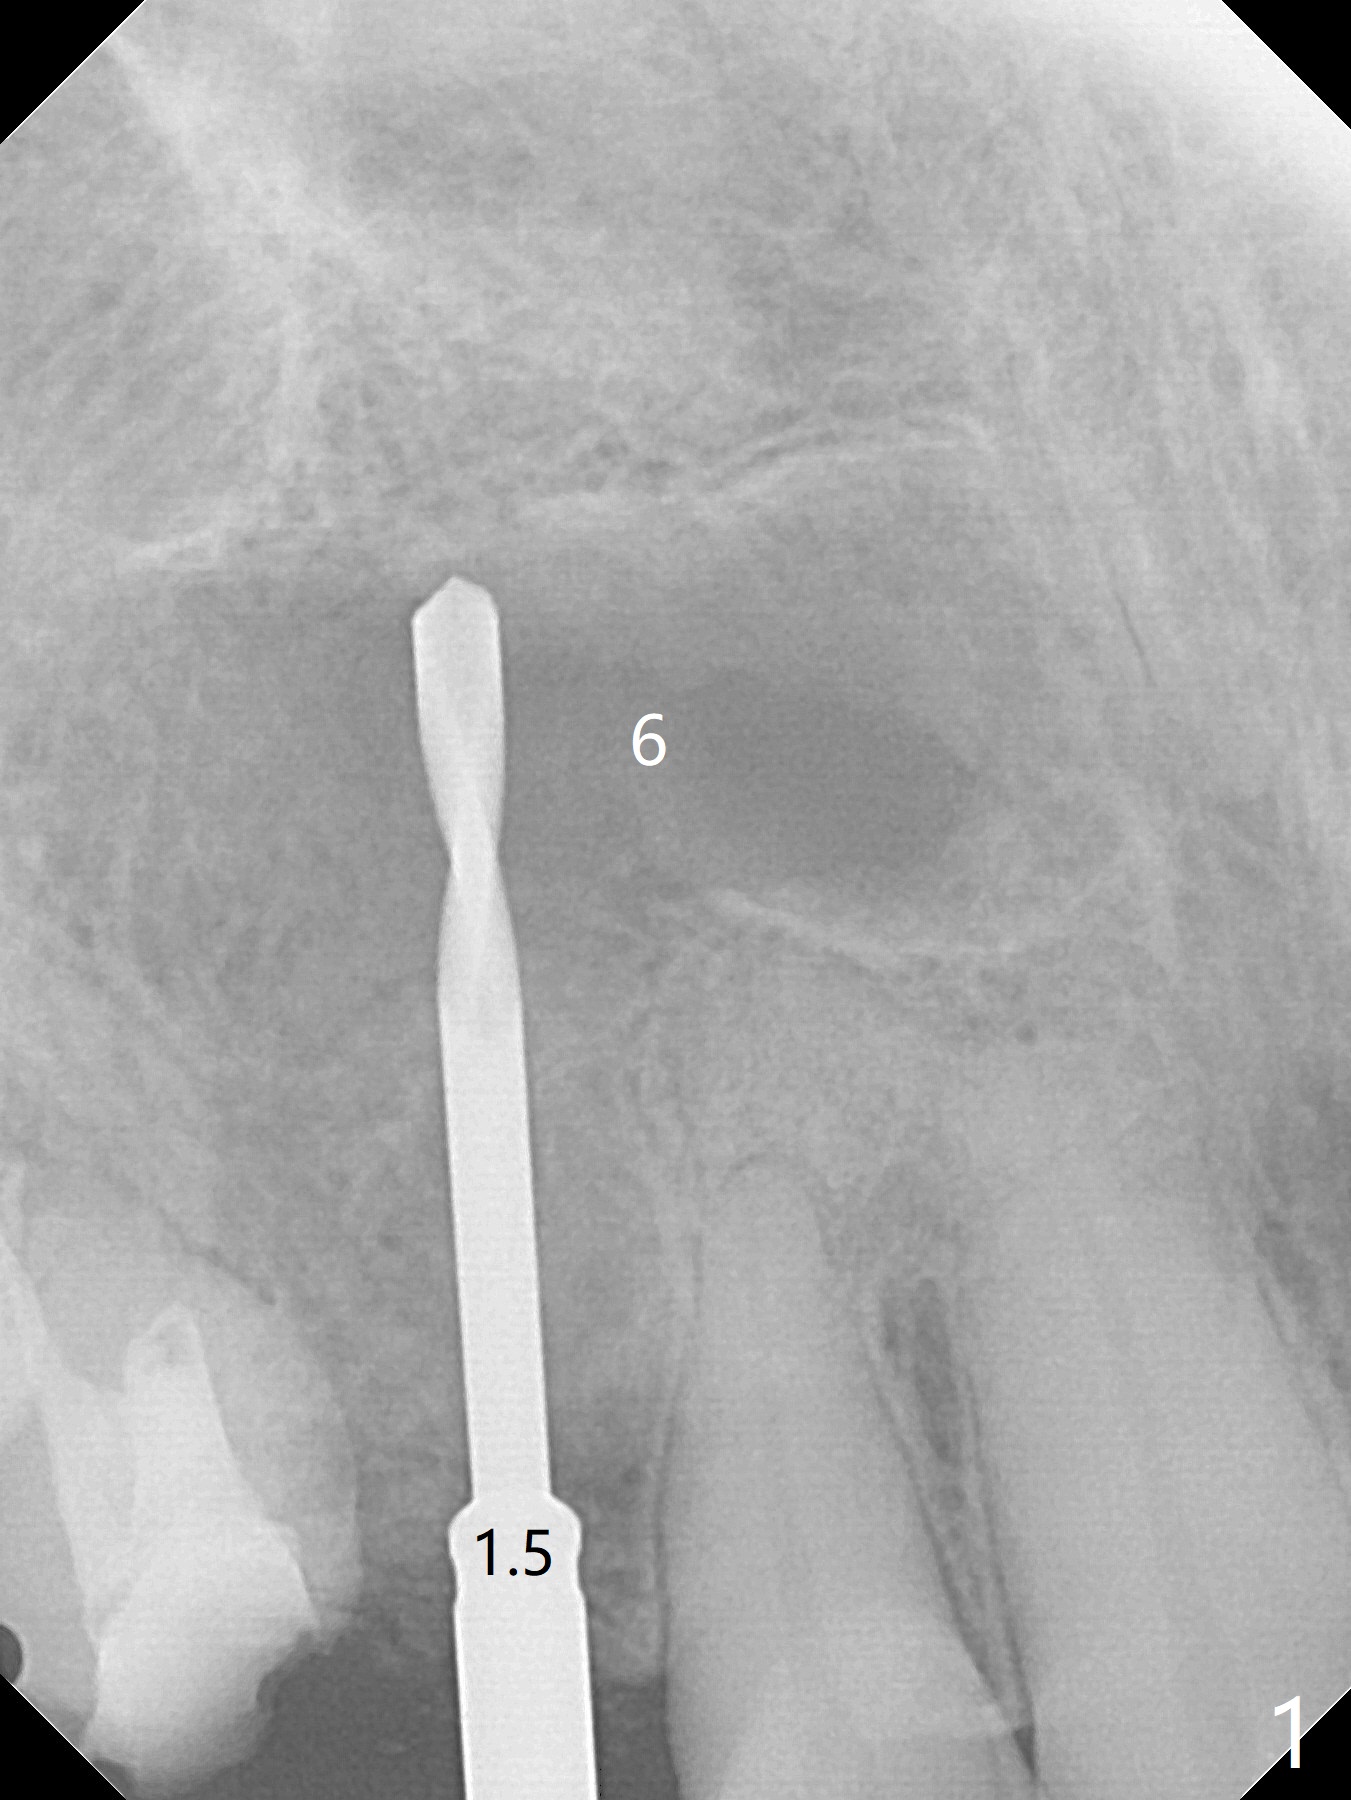

Osteotomy starts with guide and 2.2 mm drill for initial 3.5 mm palatal. A semilunar incision is made buccal to remove the impacted canine (#6 by sectioning). With direct vision buccal and palatal, the final osteotomy is finished free hand with 1.2 and 1.5 mm drills. Initially buccal perforation occurs, the osteotomy route is corrected later (Fig.1). When a 2.5x15 mm 1-piece implant is being placed, it perforates into the buccal concavity again. After redirection, the trajectory seems to be acceptable (Fig.2: CT coronal section). Three coronal implant threads are exposed partially palatal (Fig.3: CT 3-D palatal view). The implant is then turned 2-3 times with insertion torque reaching 40 Ncm. The incision is closed with suture following Osteogen plug placed in the most coronal portion of the socket (Fig.4 P) and allograft (*) in the remaining socket around the apical portion of the implant as well as palatal. The incision does not heal 1 month postop (Fig.5). PRF membrane will be placed next visit. Next visit the wound in fact is healing (Fig.6). PRF is unnecessary. The patient will return for impression 3 months postop. To be cosmetically pleasing, prepare local anesthetic and Laser for gingivectomy (Fig.7 red curved line). There is no bone loss around the implant 3.5 months postop (Fig.8). With topical, minor gingivectomy with laser creates papillae mesial and distal to the implant (Fig.9, 10 (incisal view)). After reline, there is appearance of a canine (Fig.11). The patient returns for impression 5 months postop; there is bone around the apex of the implant (Fig.12 *). The hard and soft tissues remain healthy when final restoration is delivered (Fig.13,14). The buccal plate reforms and #6 socket heals 12 months postop (6 months post cementation, Fig.15). The gingiva remains healthy at #4-6 nearly 2 years post cementation (Fig.16).